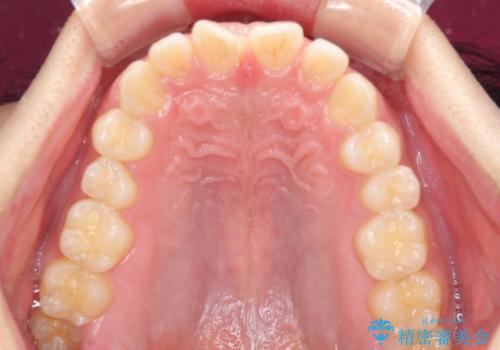

デコボコとディープバイトを治したい インビザラインによる矯正治療

- 前歯のデコボコや隙間と深い咬み合わせ(ディープバイト)を気にして来院された患者様です。

インビザラインによる上下歯列の側方拡大と後方移動、IPR(歯と歯の間を削る)にるスペースの獲得により、デコボコとディープバイトを改善することとしました。

気になっていたデコボコや隙間は改善し、きれいな歯列に整えることができました。

咬合力が非常に強い方であったため、これ以上のディープバイトの改善は困難となりました。